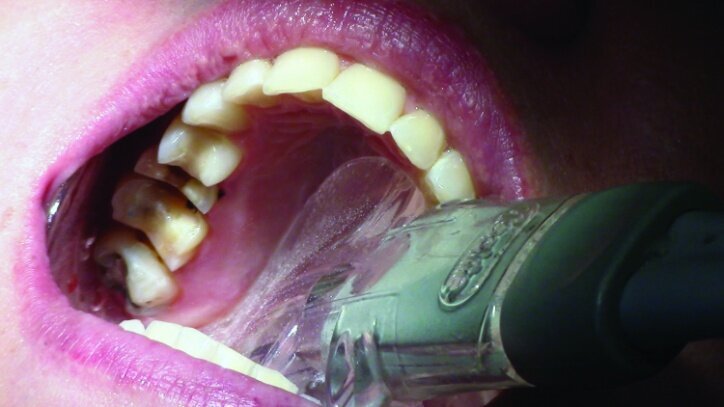

This patient presented for restorations of teeth #3 and #4 (Fig. 1a). Because of the size of the existing restorations, these teeth were diagnosed as structurally compromised (Figs. 1b, c). The prognosis without treatment was fair.

The restorations were to be completed with PlanScan chairside CAD/CAM technology in the same visit.

Local anesthesia was achieved with 1.7 cc 2 per cent Lidocaine with 1:100,000 epi, buffered with Onset sodium bicarbonate inj., 8.4 per cent, USP neutralizing additive solution.

Depth guide cuts were made using a 330 bur, which has a 2 mm cutting surface (Figs. 2a–3b). This ensures 2 mm of occlusal reduction to accommodate 2 mm of material thickness on the occlusal surface of the restoration.